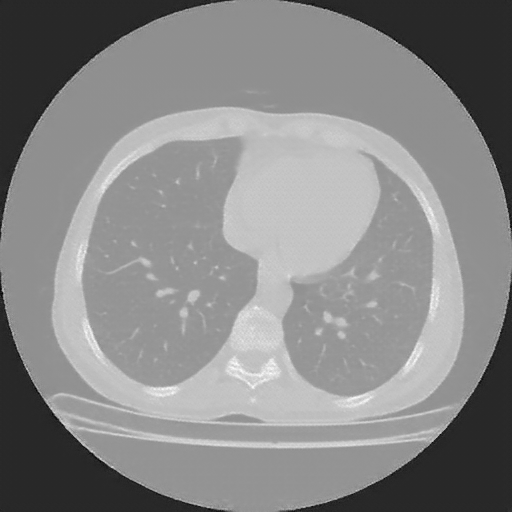

Targeted Slice 70 - Lung Window Analysis (Generated vs Real Venous)

0.609

Lung SSIM

106.8

Lung RMSE

53.6

Lung MAE

Average Lung Window Metrics Across All Slices (112 slices) - Generated vs Real Venous

0.626

Lung SSIM (Avg)

107.5

Lung RMSE (Avg)

51.7

Lung MAE (Avg)

Reconstructed NATIVE CT scan (cycle consistency)

Lung window (WL -600, WW 1500 β†’ Low βˆ’1350, High +150)